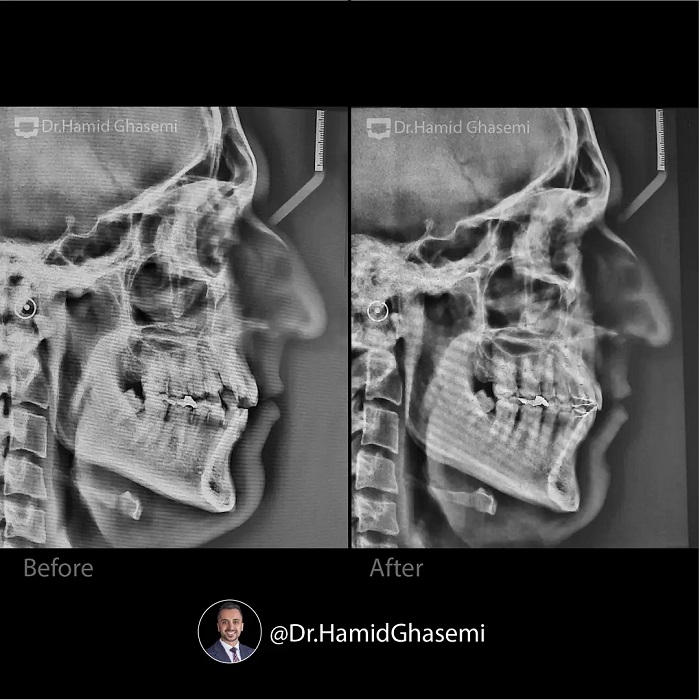

درمان ارتودنسی بدون جراحی فک و بدون کشیدن دندان در کیس همراه با کنت شدید اکلوزال و لترال اپن بایت با استفاده از تکنیک MEAW در مدت ۲۴ ماه انجام شد.

Non surgical and non extraction orthodontic treatment of case with sever occlusal cant and huge lateral openbite done using MEAW technique within 24 months.